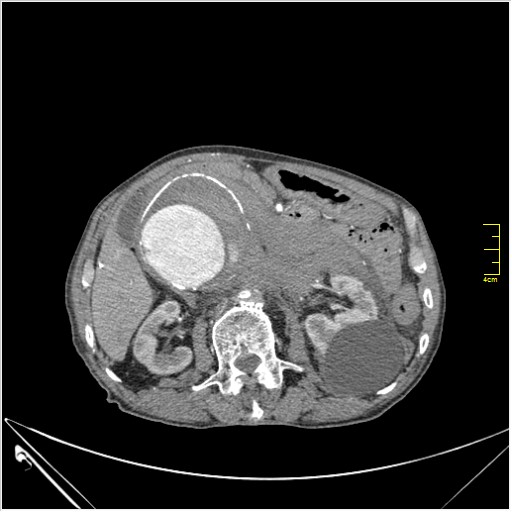

Пациент Т. 64 года, обратился на КТ брюшной полости амбулаторно (!), по направлению семейного врача с диагнозом abdominal mass, буквально: образование брюшной полости.

ИМХО простые кисты.Uzgraph писал(а):Случай интересный - ногу сломишь. Вроде бы анефризма брюшной аорты(особенно по УЗИ), но что тогда за образования сидят на левой почке - онкология?

Huge abdominal aorta aneurism. Simple renal cortical cysts (Bosniak type 1).